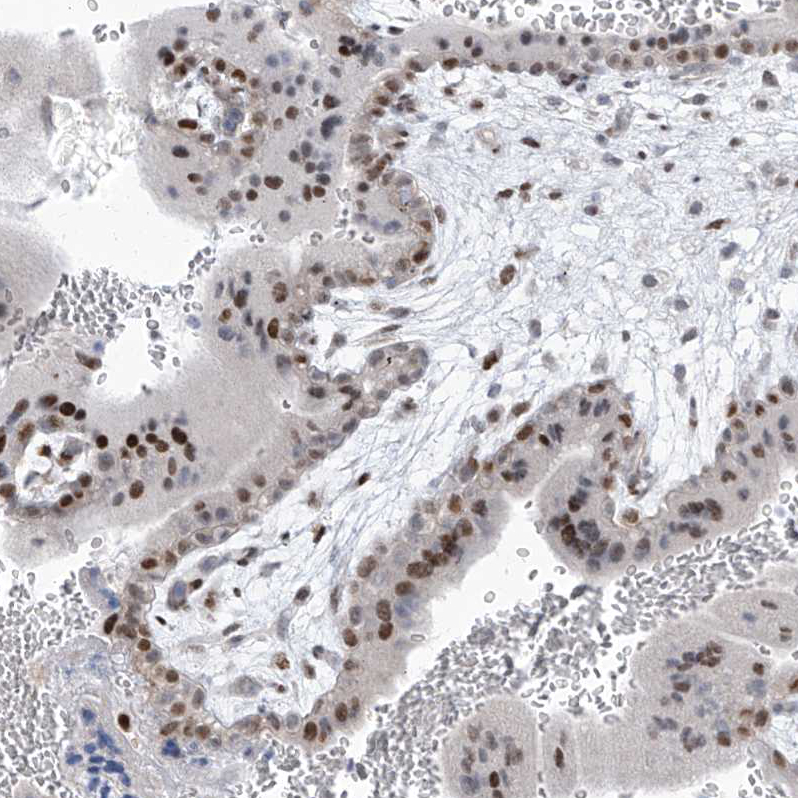

Immunohistochemical staining of human testis shows moderate nuclear positivity in cells in seminiferous ducts.